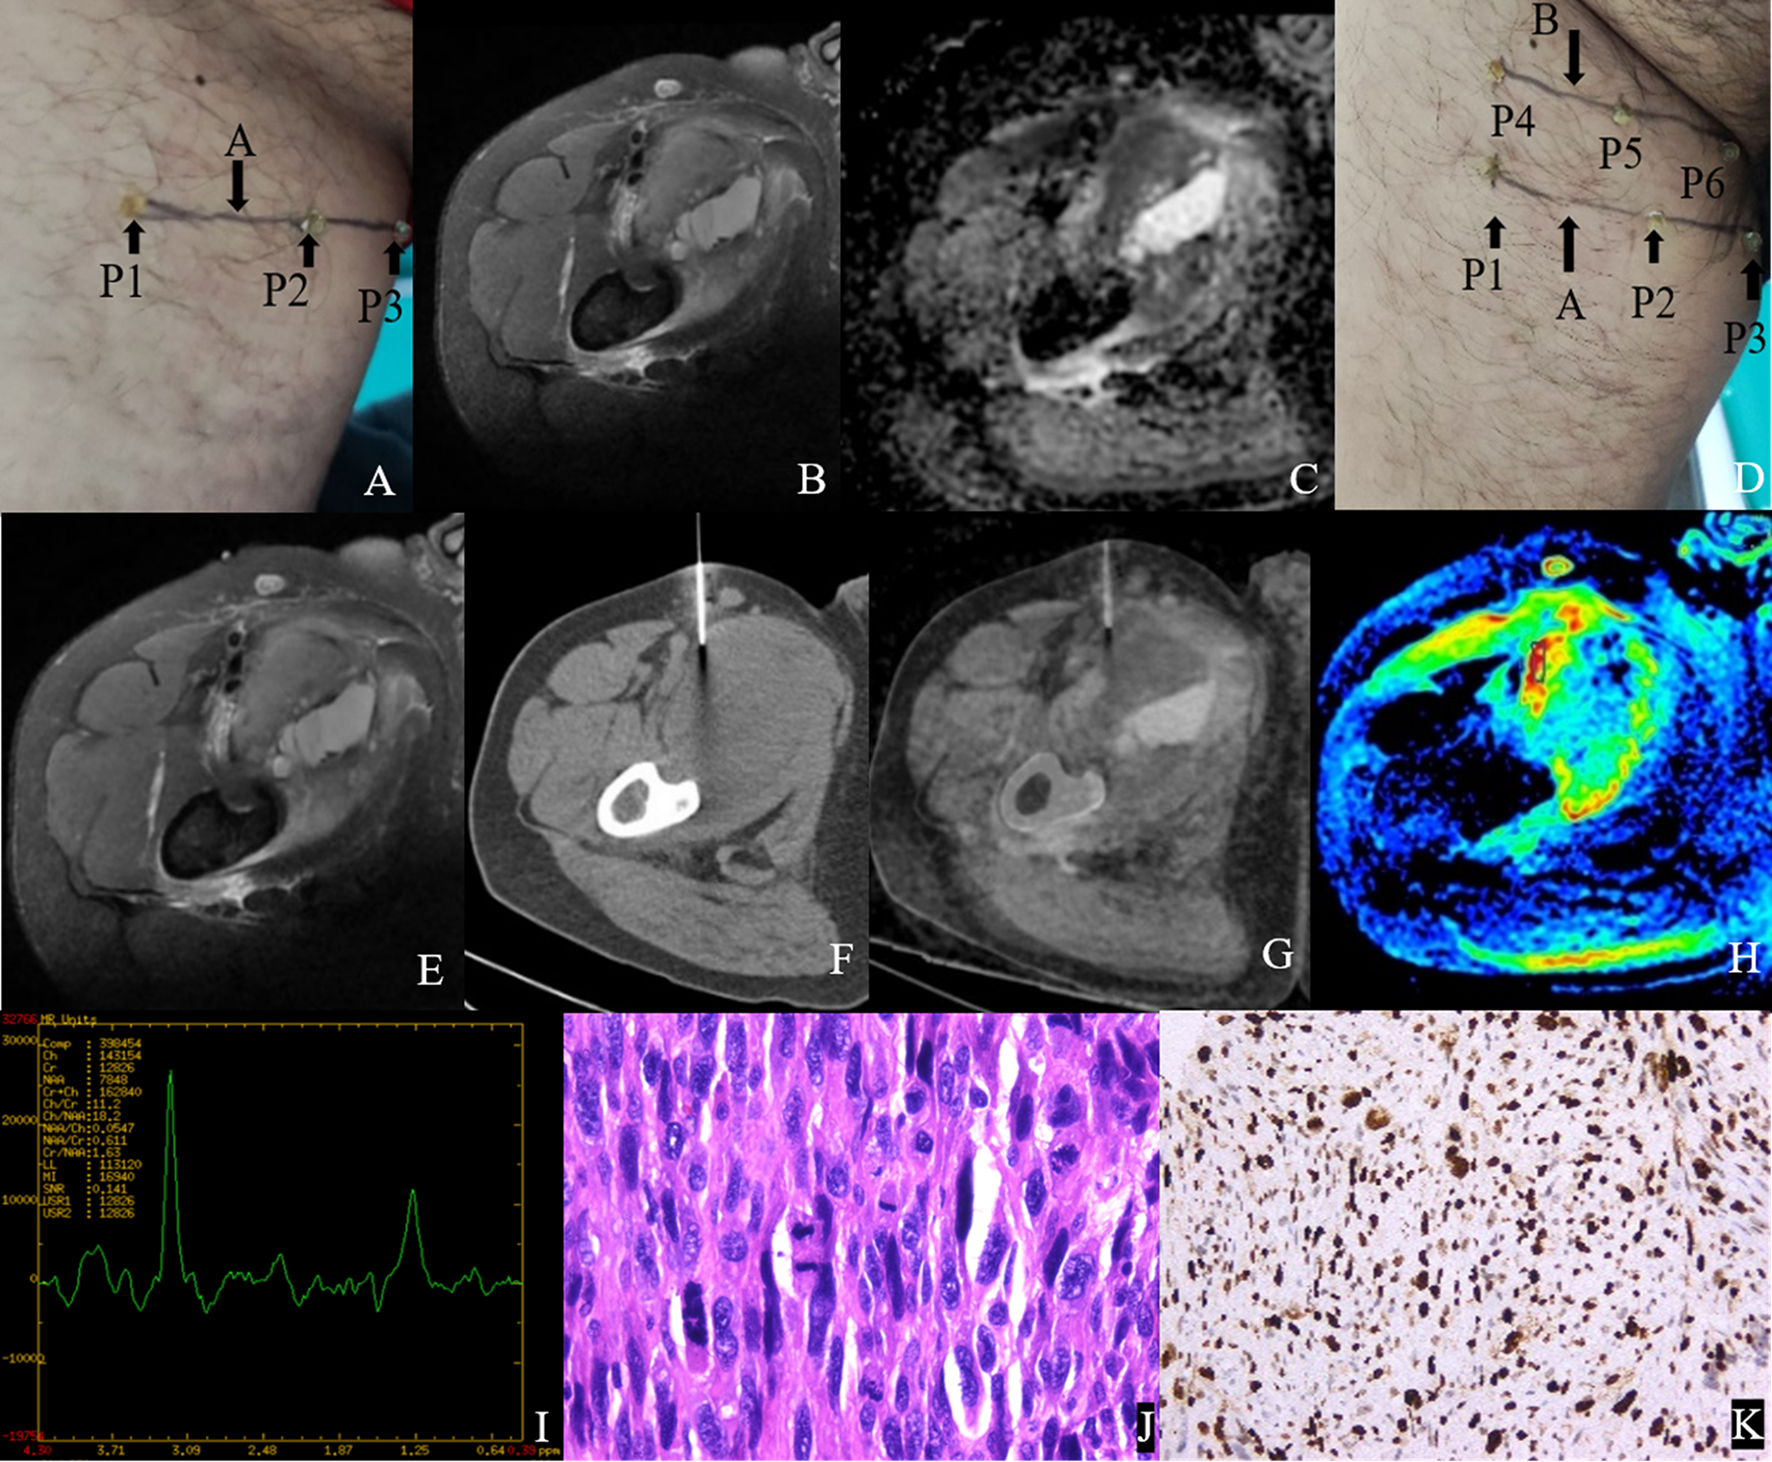

Figures 4 and 5 show the features of the CT-MR fusion registration images, pathological diagnosis, and Ki-67 LI images of the histologically confirmed pleomorphic leiomyosarcomas and myxofibrosarcomas.

Figure 4. Male, 47Y, Pleomorphic leiomyosarcoma of the right thigh, G3. (A) Body surface positioning marks before MRI examination; (B, C) Targeted slice, chosen by Axial T2WI-FS and ADC image; (D) Mark the targeted slice on body surface; (E) A second time Axial T2WI-FS scan to confirm the target slice; (F) CT guided biopsy at target slice; (G) CT-MRI image fusion at target slice; (H) Draw ROI to obtain DWI quantitative parameters, ADCmin: 0.725×10–3 mm2/s, ADCmean: 0.929×10–3 mm2/s; (I) 1H MR spectrum, Cho/Cr:11.2; (J) Histological images of biopsy specimens, Grade 3, HE×200; (K) Ki67 index 70%.